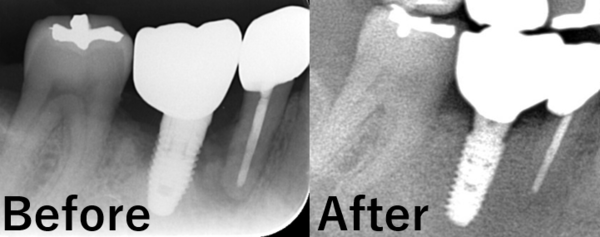

右下6番相当部のみのX線写真です。

6番インプラント周囲の骨欠損が確認できます。

また、5番の根管治療が行われている歯の根の先にも骨吸収が疑われる所見が見られます。

いくつかの診査と患者様との相談の結果、今回は5番の根管治療は行わず、最低限必要な介入にとどめて治療を進める方針となりました。

今回、残念ながらインプラントの埋入位置が不適切であったため、インプラントは一度除去し再治療を行うという判断になりました。